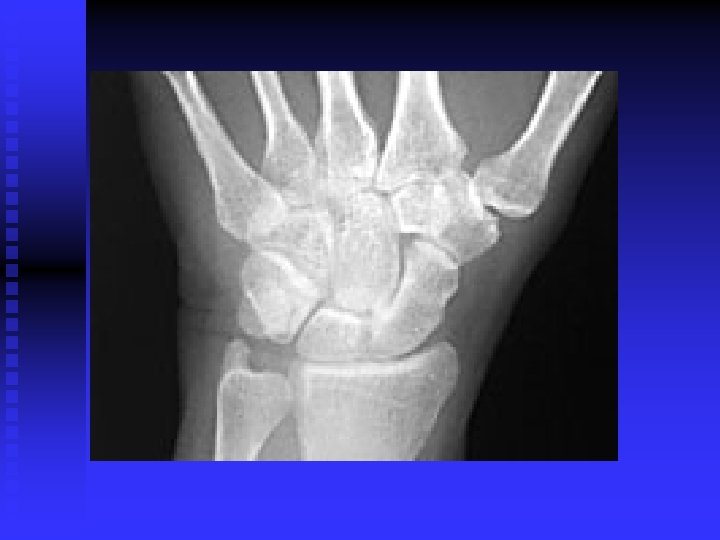

Carpal Tunnel Syndrome n n Median nerve compression within the carpal tunnel is the most common peripheral nerve entrapment syndrome. Any condition that decreases the cross sectional area of the carpal tunnel or increases the volume of its contents may cause the pathology. EX: lunate dislocation; distal radius fracture, sustained flexion or extension postures, fluid retention, synovitis